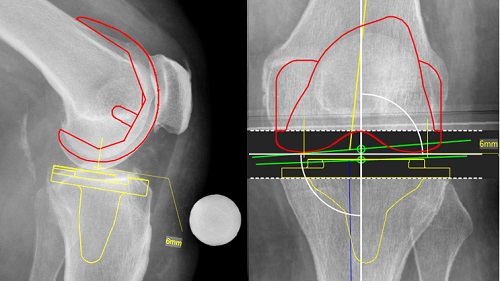

Việc lập kế hoạch được thực hiện đồng thời dựa trên hình ảnh X quang của toàn bộ chi dưới ở mặt phẳng thẳng và một phần của mặt phẳng bên. Cách tiếp cận này cho phép tối ưu hóa đánh giá đối với lồi cầu sau xương đùi.

Tất cả các chiều của diện cắt đều được xác định và mọi sai lệch gióng trục đều được xác định và sửa chữa một cách tự động sau khi các điểm mốc giải phẫu có liên quan được tự động nhận dạng bằng chức năng “Autoplan Knee”

Phương pháp thay khớp gối bán phần có nhiều ưu điểm hơn so với thay toàn bộ khớp gối do chỉ lấy bỏ phần sụn khớp bị hỏng còn các tổ chức sụn, xương lành, dây chằng chéo sẽ được bảo tồn hoàn toàn.

Với sự hỗ trợ của phần mềm MediCAD Knee, các bác sĩ dễ dàng đo đạc, cắt xương, lên kế hoạch phẫu thuật chính xác và giảm rủi ro trong quá trình phẫu thuật.